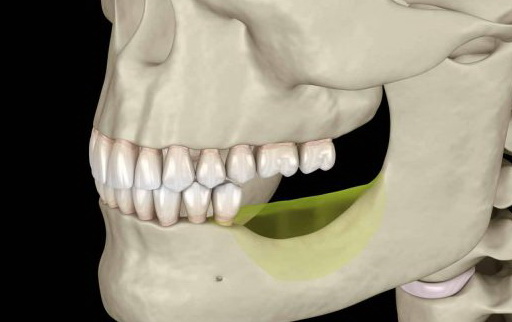

In order to chew smoothly, teeth have the characteristic of being close to each other. Therefore, if the teeth are left unattended after extraction, the teeth on the opposite side will extend and grow towards the missing teeth area, and the adjacent teeth on the left and right will also gather towards the missing teeth area, causing irregular teeth. Condition.

Problem 4: Alveolar bone atrophy

After tooth loss, the alveolar bone will gradually shrink, making the face sunken, haggard and old. After dental implantation, the bite force can be transmitted downward through the artificial tooth root, thus maintaining the health of the alveolar bone and slowing down the rate of atrophy.